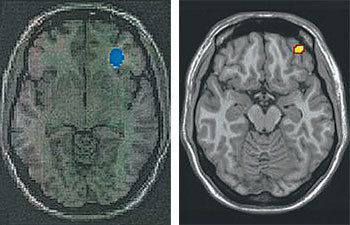

일반인에 비해 활동성이 높은 코카인 중독자의 대뇌 영역(왼쪽 사진)과 일반 사용자에 비해 활동성이 높은 인터넷 게임 과다 사용자의 대뇌 영역(오른쪽 사진). 유사한 부위의 뇌 기능이 떨어졌다는 것을 보여준다. 사진 제공 분당서울대병원

인터넷 게임 중독자의 뇌가 마약 중독자의 뇌와 유사하게 활동한다는 사실을 국내 연구진이 밝혀냈다.

김상은 분당서울대병원 핵의학과 교수팀은 “양전자방출단층촬영(PET) 기법으로 인터넷 게임 정상 사용자 9명과 게임 과다 사용자 11명의 대뇌 포도당 대사 등을 측정한 결과 인터넷 게임 과다 사용자는 오른쪽 안와 전두피질, 왼쪽 미상핵, 오른쪽 도회의 기능이 정상인보다 떨어진다”고 9일 밝혔다. 안와 전두피질, 미상핵, 도회는 각각 충동 조절, 보상 처리, 중독을 담당하는 인지 기능을 관장하는 대뇌영역이다. 인터넷 게임을 과도하게 하면 뇌의 기능이 떨어지고 이를 활성화하기 위해 특정 부위의 포도당 대사가 활발해진다. 약물 남용, 도박 중독, 충동조절장애를 겪는 환자들의 뇌도 유사한 작동 기제를 보인다. 김 교수의 연구 결과는 내년 해외 과학저널인 ‘씨엔에스 스펙트럼스(CNS Spectrums)’에 게재될 예정이다.